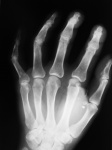

Сверхкомплектные косточки.

Перелом у основания основной фаланги 5 пальца.В мягких тканях, похоже на металл.